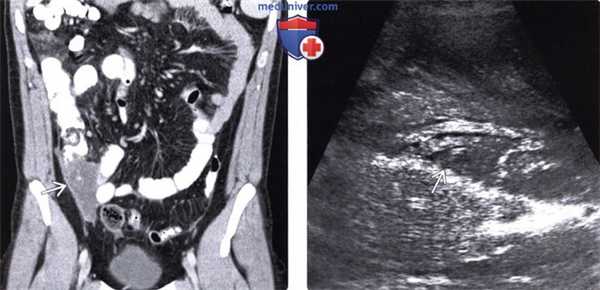

(Слева) На корональной КТ с контрастным усилением - самые ранние признаки псевдомиксомы брюшины, которые включают в себя наличие доминирующего муцинозного очага в нижних отделах справа, возникшего в результате разрыва мукоцеле аппендикса. Других вторичных очагов не определяется.

(Справа) На УЗИ в сагиттальной плоскости у пациента с псевдомиксомой брюшины визуализируется вторичный очаг возле печени. Несмотря на то, что очаги выглядят кистозными на КТ, на УЗИ они определяются как эхогенные образования солидного характера.